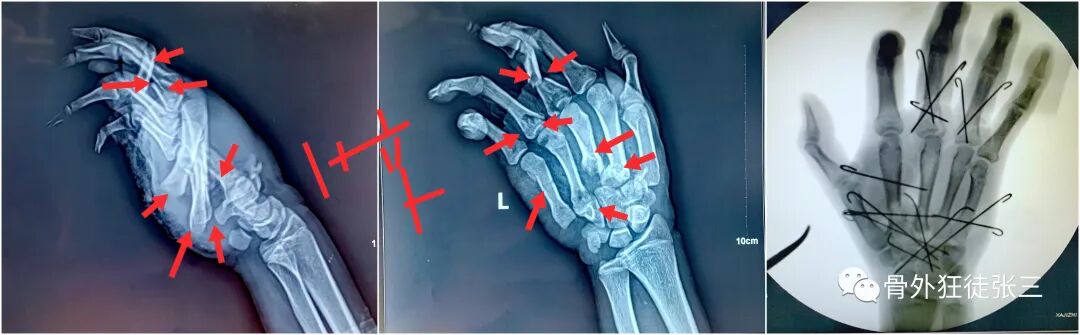

病例6,开放性第2345掌骨骨折,克氏针支架

病例12,严重开放性手外伤保肢,克氏针固定。

病例23,严重复杂手外伤,多发骨折,克氏针固定